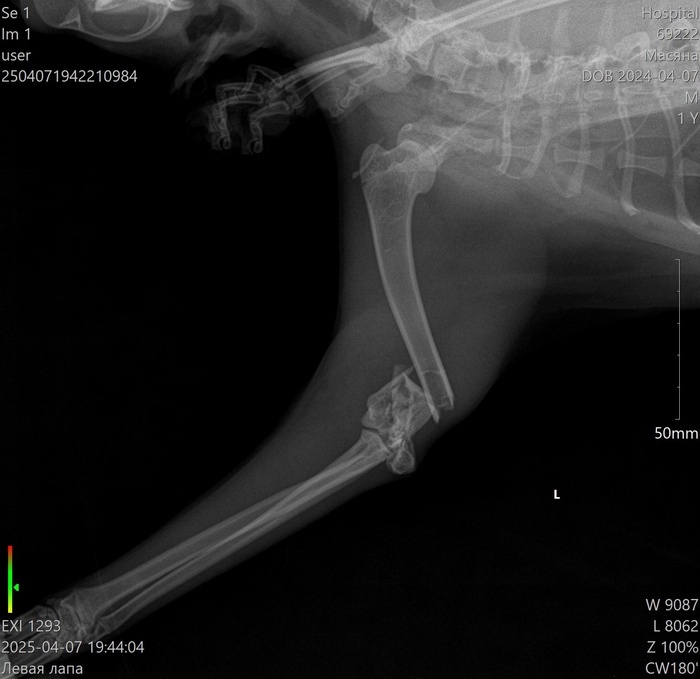

Верю, что тут есть профильные специалисты. Позавчера не уследил за кошкой, забыл закрыть форточку на какие-то полчаса, выпрыгнула с пятого этажа и крайне неудачно. Переломаны левые передняя и задняя лапы. Но если по задней лапе прогноз хороший, то по передней хирург сказал, что сустав раздроблен, и конечность он будет сращивать жестко и под углом. Кошке всего полтора года, очень жизнерадостная - даже под опиоидным обезболивающим уже сегодня сама сходила по-маленькому, и пытается встать и бегать за остальными двумя кошками (у нас их три).

Можно ли по рентгеновским снимкам определить - удастся ли сохранить подвижность лапке? Если искать хирурга, который за это возьмется.